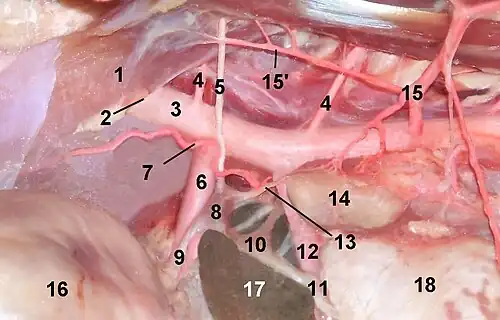

Die arterielle Versorgung wird über drei Zuflüsse gewährleistet: Die Arteriae suprarenales superiores entspringen der Arteria phrenica inferior, die Arteria suprarenalis media entspringt direkt der Aorta abdominalis und die Arteria suprarenalis inferior stammt aus der Arteria renalis.[5]

Die venöse Drainage erfolgt über eine Vena centralis, die aus dem Hilum der Nebenniere austritt. Das venöse Blut der linken Nebenniere gelangt über die Vena suprarenalis sinistra in die Vena renalis und von dort in die Vena cava inferior, während das Blut der rechten Nebennierenrinde direkt über die Vena suprarenalis dextra in die Vena cava inferior gelangt.